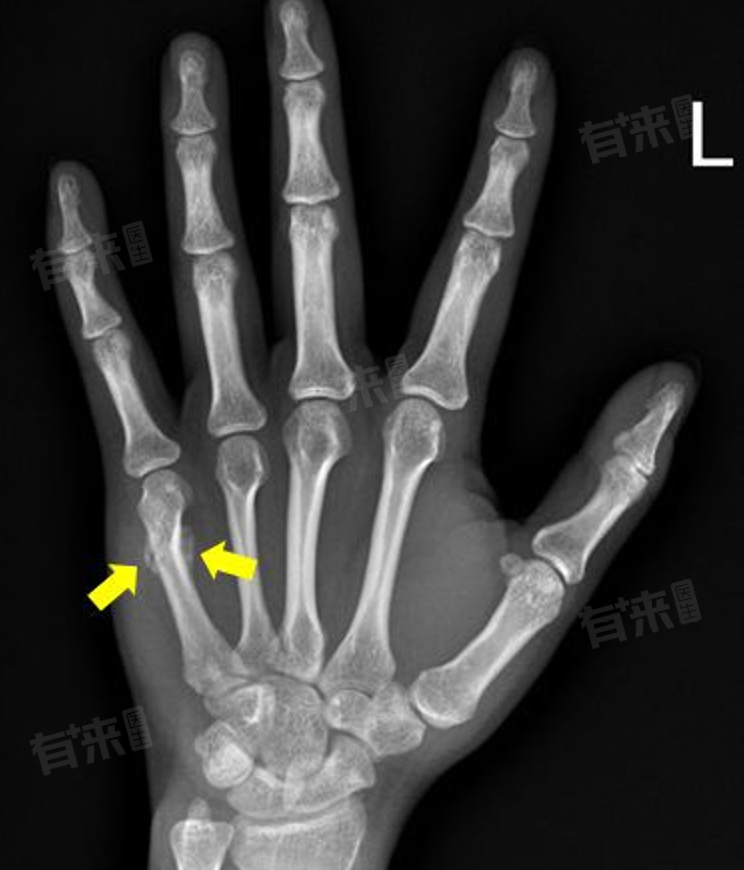

- X线片检查:这是最直观、最准确的判断骨痂生长的方法。在X线片上,可以看到骨折端周围有密度较高的阴影,即为骨痂。随着骨痂的生长,会逐渐连接骨折端,形成桥梁状结构,最终使骨折愈合。